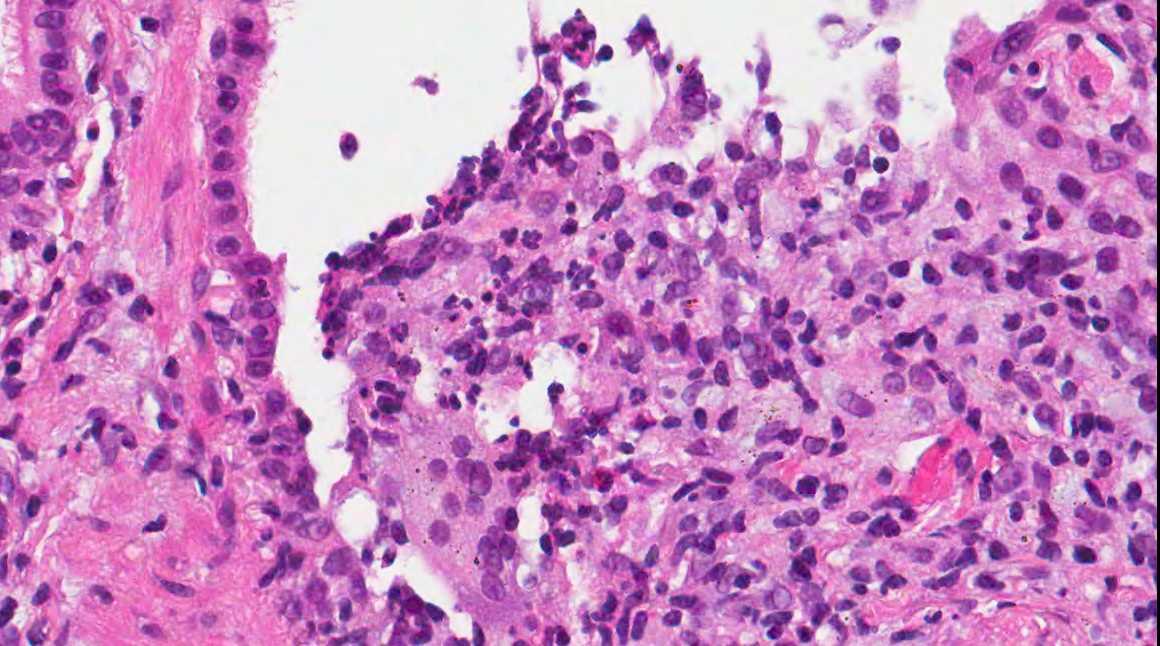

A 71 year old man with recent history of meningitis presented with recurrent episodes of pneumonia. High resolution CT scans showed crazy paving and tree in bud images. The patient underwent a transbronchial biopsy.

Diagnosis: Aspiration with granulomatous bronchiolitis and lipoid pneumonia

Aspiration of particulate matter, traditionally observed at autopsy, has also been described in debilitated patients, who often have a history of recurrent pneumonia, which is often unrecognized (Am J Surg Pathol 2007;31:752, Am J Surg Pathol 2010;34:1456). It usually (88%) shows bronchiolitis obliterans organizing pneumonia, often with multinucleated giant cells, acute bronchopneumonia / bronchiolitis or suppurative granulomas. Foreign material is usually but not always present (Am J Surg Pathol 2011;35:426).

The differential diagnosis of pulmonary granulomatous inflammation is broad and requires special stains, culture and clinical correlation (Ann Diagn Pathol 2003;7:127, Histopathology 2007;50:289).

Lipoid pneumonia is often an incidental postmortem finding associated with debilitating disease. The lipid may be exogenous (from nasal sprays or inhalation of other lipid containing substances) or endogenous (bronchial obstruction).

A 71 year old man with recent history of meningitis presented with recurrent episodes of pneumonia. High resolution CT scans showed crazy paving and tree in bud images. The patient underwent a transbronchial biopsy.

Diagnosis: Aspiration with granulomatous bronchiolitis and lipoid pneumonia

Aspiration of particulate matter, traditionally observed at autopsy, has also been described in debilitated patients, who often have a history of recurrent pneumonia, which is often unrecognized (Am J Surg Pathol 2007;31:752, Am J Surg Pathol 2010;34:1456). It usually (88%) shows bronchiolitis obliterans organizing pneumonia, often with multinucleated giant cells, acute bronchopneumonia / bronchiolitis or suppurative granulomas. Foreign material is usually but not always present (Am J Surg Pathol 2011;35:426).

The differential diagnosis of pulmonary granulomatous inflammation is broad and requires special stains, culture and clinical correlation (Ann Diagn Pathol 2003;7:127, Histopathology 2007;50:289).

Lipoid pneumonia is often an incidental postmortem finding associated with debilitating disease. The lipid may be exogenous (from nasal sprays or inhalation of other lipid containing substances) or endogenous (bronchial obstruction).